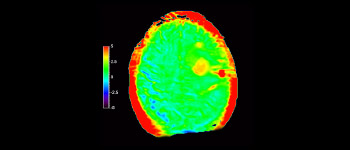

In een samenleving waarin veel neurologische aandoeningen voorkomen, streeft Philips naar een superieure duidelijkheid op het gebied van diagnoses en behandelingsbegeleiding voor alle patiënten. Hoewel MR vandaag de dag de gouden standaard is in neuro-oncologische beeldvorming, is er nog ruimte voor verbetering van de nauwkeurigheid bij het beoordelen van tumoren en follow-ups. 3D APT (Amide Proton Transfer) is een unieke, contrastvrije MR-beeldvormingsmethode voor de hersenen als antwoord op de vraag naar betrouwbaardere diagnostiek in de neuro-oncologie. 3D APT maakt gebruik van de aanwezigheid van endogene celeiwitten voor het produceren van een MR-signaal dat direct correleert met celproliferatie, een marker voor tumoractiviteit. 3D APT kan getrainde medische professionals ondersteunen bij het maken van onderscheid tussen laaggradige en hooggradige gliomen en tussen de ontwikkeling van de tumor en het effect van de behandeling1.

met 3D APT